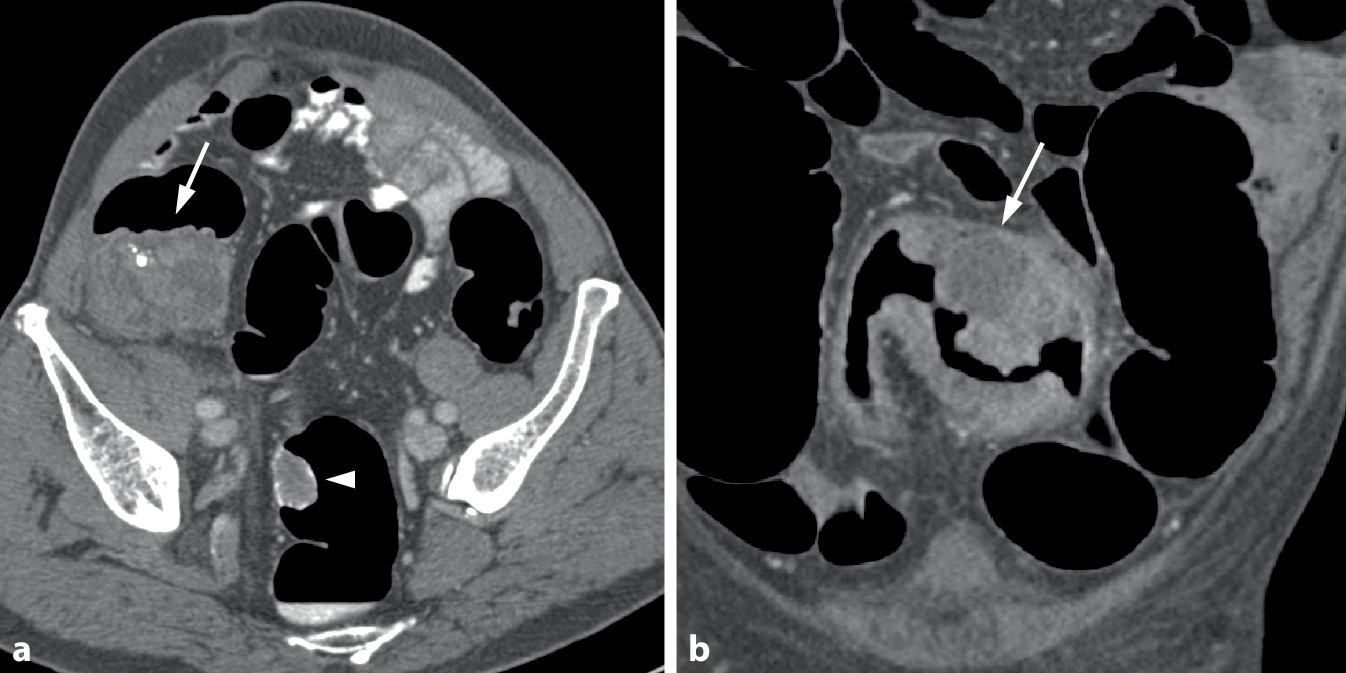

Bei polypösen Tumoren finden sich meist große, breitbasige, sessile Raumforderungen von über 3 cm Größe, typischerweise mit einem lobulierten Aspekt (Abb. 5). Durch Tumornekrosen kann es zur Ausbildung von Ulzerationen kommen.

Abb. 5

Polypoides Karzinom im Colon sigmoideum. a Die endoluminale 3D-Ansicht einer polypoiden Raumforderung mit lobuliertem Aspekt (Pfeil). b Das axiale 2D-Bild zeigt eine fokale polypoide Wandverbreiterung mit weichteildichter Struktur nach Kontrastmittelapplikation (Pfeil). Die zentrale Hypodensität spricht für eine muzinöse Komponente

Auf 2D-CT-Bildern zeigen kolorektale Karzinome eine ausgeprägte Wandverbreiterung mit meist homogener weichteildichter Binnenstruktur. Sie überschreitet oftmals eine Breite von 2 cm. Die durchschnittlichen CT-Dichtewerte von Karzinomen liegen auf nativen 2D-Bildern bei rund 43 HU. Nach intravenöser Kontrastmittelapplikation zeigen kolorektale Karzinome ein deutliches Kontrastmittel-Enhancement auf ca. 91 HU [13]. Hypodense Areale innerhalb von Karzinomen können durch Tumornekrosen bzw. Einschmelzungen bedingt sein. Sie finden sich allerdings auch bei muzinösen Karzinomen (Abb. 6). Nach Fecal Tagging kann es an der Tumoroberfläche zu Ablagerungen von oralem Kontrastmittel, sog. „contrast coating“, kommen.

Abb. 6

Muzinöse Tumoren und Tumornekrosen. a Parakoronares 2D-Bild eines muzinösen Zökumkarzinoms. Der polypoide Tumor weist eine inhomogene, teils hypodense Struktur auf (Pfeil). Zu beachten ist der große synchrone Polyp im distalen Sigma (Pfeilspitze). b Koronares 2D-Bild eines stenosierenden Sigmakarzinoms. Innerhalb der tumorösen Wandverbreiterung zeigt sich ein umschriebenes hypodenses Areal als Zeichen einer Tumornekrose bzw. Einschmelzung (Pfeil)